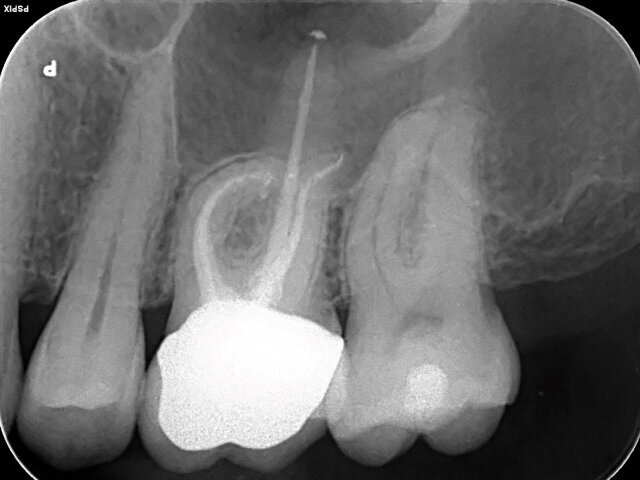

Kanálky byly nejprve zprůchodněny k apexu pomocí nástrojů Readysteel K-Flexofile 08 a 10 technikou balancované síly (obr. 2). Pracovní délka byla určena apexlokátorem.

Podařilo se lokalizovat i kanálek MB2 pomocí Dentsply Sirona LN Tungsten Steel vrtáčků. Kanálek MB2 byl nejprve zprůchodněn Readysteel K-Flexofile (obr. 5).

Při zavedení posledního použitého nástroje ProTaper Gold do kanálku MB1 bylo zjištěno, že se MB2 spojuje s MB1 4 mm před pracovní délkou MB1 – do MB2 byl zaveden Readysteel K-Flexofile. Kanálek MB2 byl opracován až ke spoji do velikosti F2 stejným způsobem jako ostatní kanálky (obr. 6).